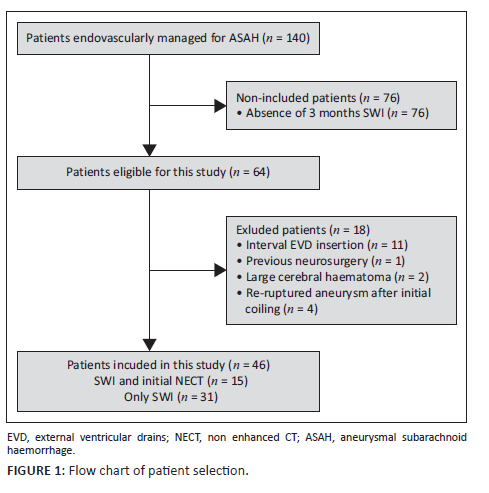

This was a retrospective, analytic, descriptive study of patients with ASAH managed at Inkosi Albert Luthuli Hospital, KwaZulu-Natal, between 01 June 2015 and 30 June 2019. The neurosurgical department offers services for both endovascular and microsurgical clipping of ASAH. Patients who underwent confirmatory initial CT brain imaging shortly after ASAH at their base hospitals and subsequent endovascular repair of the causative aneurysm were considered. Of these, all patients who underwent the same routine MRI brain sequences (including SWI) at 3 months post endovascular repair were included (Figure 1). Patients who had previous intracranial surgery, haemorrhage, trauma or malignancy prior to the initial ASAH or between the repair of the causative aneurysm and the acquisition of the SWI study were excluded.